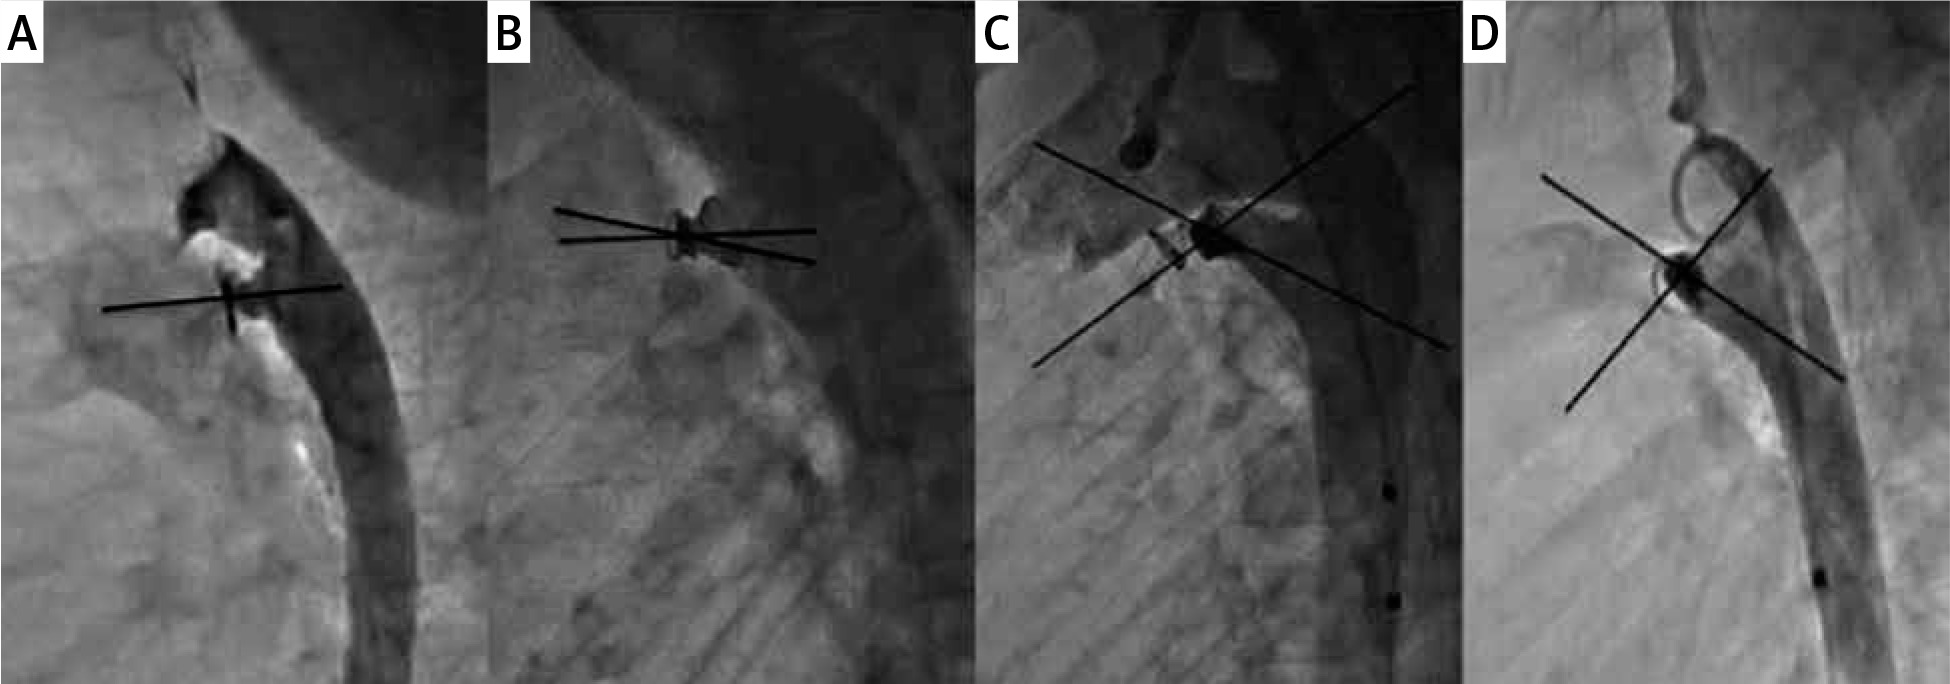

Figure 1

Orientation of the Nit-Occlud device with the length of the ductus. Legend: Varying orientations of Nit-Occlud device with the ductus. Varying device-ductal angles (0° in A, 12.5° in B, 39° in C and 88° in D) and a varying number of loops in the pulmonary artery

Further review of the Nit-Occlud cohort was performed to separate out the characteristics between those who had an angiographic residual shunt vs. those who did not (Table III). The subjects with the residual shunt in the Nit-Occlud cohort had larger PDA than those without a residual shunt. The Nit-Occlud device can position itself in the ductus in different orientations based on the length of the ductus and its diameter (Figures 1 and 2). The device ductal angle ranged from zero to 88.1 degrees (Table III, Figure 2). The device orientation, device-ductal angle, and the number of loops in the pulmonary artery did not correlate with the degree of immediate angiographic residual shunt on angiogram (Table III).

The Nit-Occlud PDA device is a spiral coil with a cone in a cone configuration that is designed to be delivered with majority of the windings delivered in the aortic side and often one loop positioned in the pulmonary side [4].We believe that the position of the rewound portion of the Nit-Occlud PDA device at the narrowest portion of the PDA is important for occlusion. However, the “proper” orientation of the Nit-Occlud PDA device along the PDA axis is not necessary for occlusion. The orientation of this device is quite variable with respect to the PDA, depending on the length and shape of the ductus. Sometimes the device orients parallel to the ductus, whereas other times, it is more perpendicular to it (Figure 1). We found that only 36.7% of devices were parallel to the axis of the PDA in our short series. The other 63.3% of Nit-Occlud devices were at angles of 12.5-88° to the long axis of the PDA, but this did not influence occlusion (Figure 2). Similarly, there can sometimes be more than one loop in the pulmonary artery end. This is especially true in the larger PDAs, where more coils of the Nit-Occlud device can inadvertently be pulled into the pulmonary artery. The tension that can safely be placed on an ADO-1 device during implantation should be avoided with the Nit-Occlud PDA device to avoid pulling too much into the pulmonary artery. Once the aortic portion is in a good position, tension should be removed from the coils, and the pulmonary portion should be deployed by pulling the delivery catheter over the delivery system, even pushing the delivery system towards the aorta, to avoid pulling too much of the device into the pulmonary artery. The number of coils in the pulmonary artery can reduce the bulk of the rewound portion at the narrowed aortic ampulla. There was more than a single coil in the pulmonary artery in 41% of patients, but this did not affect the rates of angiographic or echocardiographic occlusion.